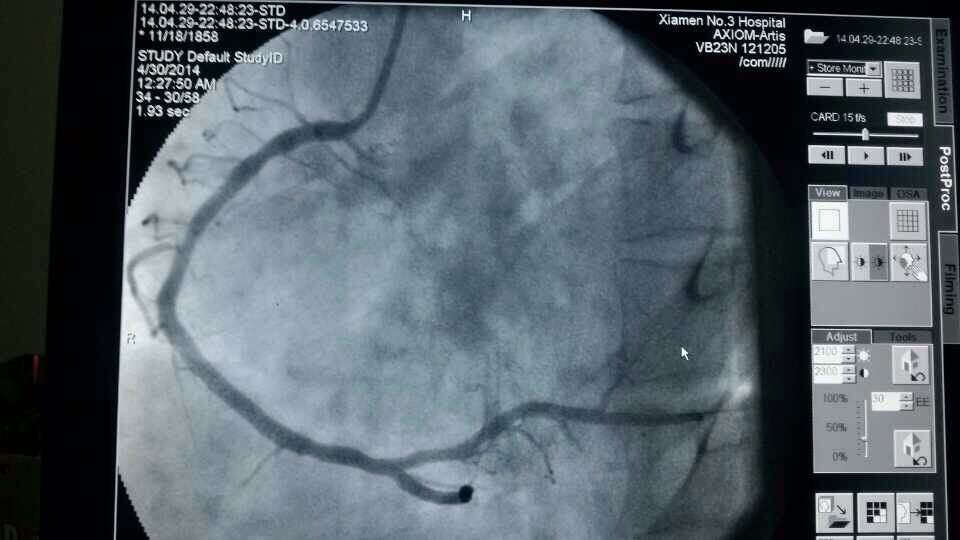

昨天仅一天的时间,厦门第三医院急诊接诊9名胸痛、心梗病人,其中一名河南来厦务工的男性患者,43岁,心脏大面积心梗;另一名翔安心梗患者送到三院时已经心衰终末期,但第三医院马上启动应急机制,心内科抢救技术团队第一时间到位,给予紧急打通血管,植入支架,才保住了两名患者的生命。